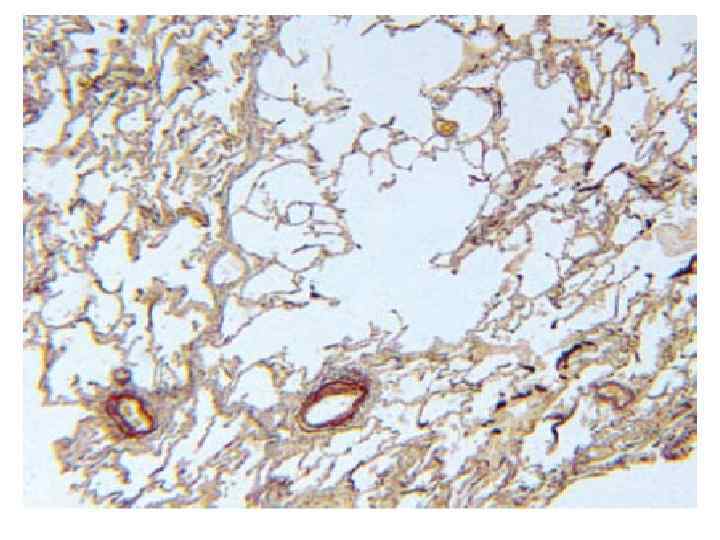

• Ацинус керілгендіктен эластикалыќ талшықтар жіңішкеріп, альвеолалық жолдар кеңейіп, олардың іргесі өзгереді. Альвеолалардың іргесі ж±қарып, тегістеледі, альвеолааралық тесіктер кеңейіп, капиллярлардың саңылауы бос қалады. Ауа жеткізетін тыныстыќ бронхиолалар да кеңейіп, альвеолалардың қалташалары тайыздайды, газалмасатын аймақтың кµлемі күрт кеміп, өкпенің вентиляциялық (ауа алмастыру) қызметі бұзылады. Ацинустардың тыныстық бөлігіндегі капиллярлар желісі т±рпайыланып, альвеола-капилляраралыќ бөгет (блок) қалыптасады. Альвеолааралық капиллярларда коллагендік талшықтар көбейіп, интракапиллярлык склероз дамиды. Бейімделу процесін бейнелейтін жаңа капиллярлар желісі пайда болады. Сонымен өкпенің созылмалы обструкциялы эмфиземасынан қанайналымының кіші шењберінде гипертония қалыптасып, ол жүректің оң жақ бөлігін ұлғайтады (өкпелік жүрек). Созылмалы эмфиземаныњ соңғы кезеңінде науқас адамда жүрек-өкпе қызметінің жеткіліксіздігіне тєн халдың бейнесі басты орын алады.

Эмфизема кезінде альвеолалар созылады, саңылауы кеңейді, біріңғай салалы бұлшықетті будалар гипертрофияланады, кейін дистрофияға ұшырайды. Эластикалық талшықтар азаяды, капилиярлар қуысы бос қалады. Микробейнесі: Өкпенің көлемі ұлғаяды, бозарады, кескенде сықыр естіледі. Идиопатиялық эмфизема кезінде бұл құбылыстың диффузды, ал салдарлық эмфизема кезінде ошақты орналасуын байқауға болады. Макробейнесі: